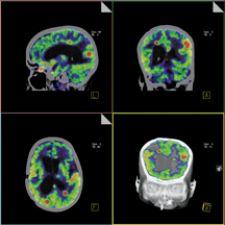

This image, acquired on Siemens' Biograph PET/CT, shows intracerebral metastases.

Similar leaps in early detection and differential diagnosis have been made in the field of neurology. Researchers involved in a large multi-institutional study1 used PET imaging with fluorodeoxyglucose (FDG) and were able to classify different types of dementia by measuring the cerebral metabolic rate of glucose (CMRglc) in various areas of the brain. The area of the brain where a decrease in metabolic rate occurred indicated different types of dementia. Those examined included Alzheimer’s disease, frontotemporal dementia and dementia with Lewy bodies, and, more than 94 percent of the time, the disease type was correctly classified using this technique.

Gary Small, M.D., professor of psychiatry and aging at UCLA Femel Institute, has also contributed to new developments in the early detection of Alzheimer’s.2 He employed Siemen’s ECAT HR and EXACT HR tomography, reportedly one of the most widely used PET systems in the world, in his research on Alzheimer’s. Based on the past discovery that certain abnormal protein deposits called amyloid senile plaques and tau neurofibrillary tangles are hallmarks of Alzheimer’s disease, he used a new tracer, FDDNP, (2-(1-6-[(2-[F-18] fluoroethyl)(methyl)amino]-2-naphthylethylidene) malonitrile, to visualize the pattern of radioactivity within the brain using FDDNP-PET scanning.